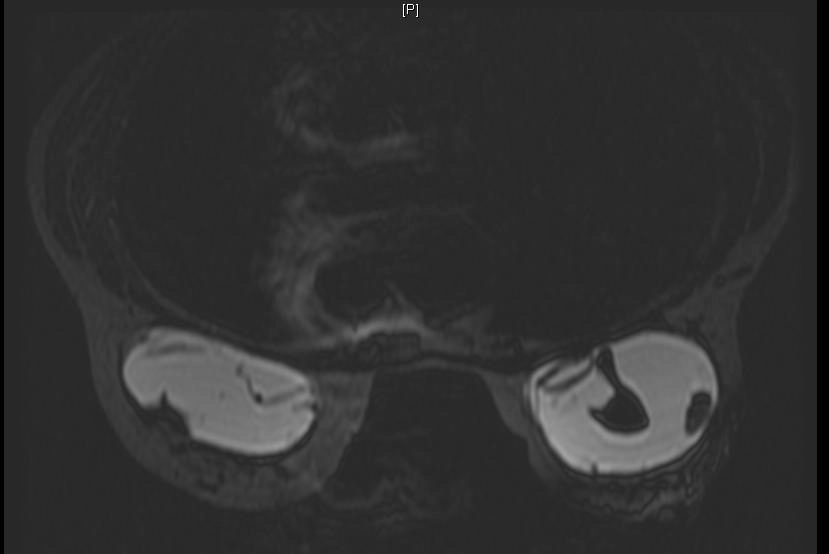

Co thắt bao xơ túi ngực (Capsular contracture)